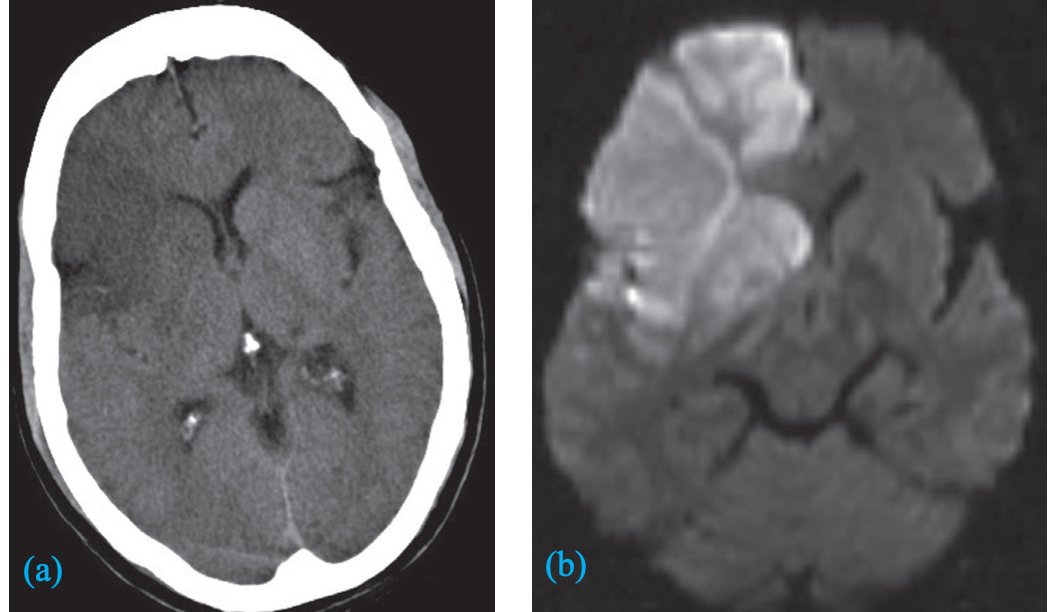

A) An unenhanced CT image showing low attenuation in the right frontal lobe and basal ganglia .

B) Diffusion-weighted MRI showing bright signal indicating an acute infarct